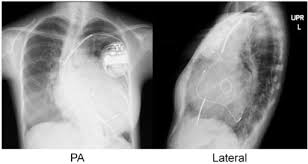

1. التقييم قبل الجراحة

يشمل الفحوصات القلبية، وتحاليل الدم، والتصوير بالأشعة المقطعية والرنين المغناطيسي.